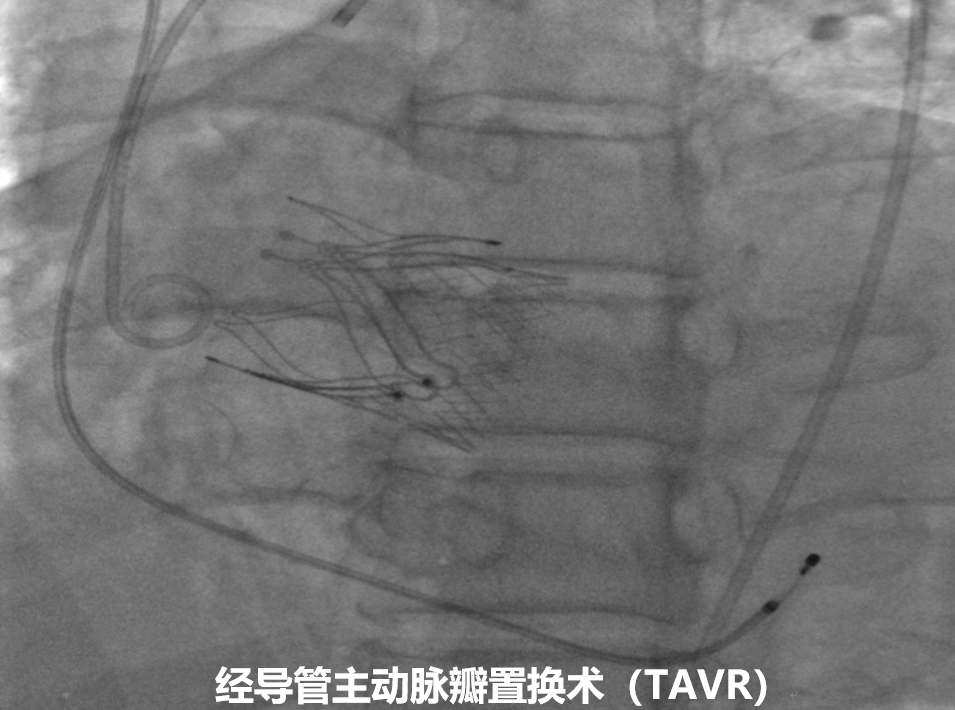

近日,青大附院心血管内科主任廉哲勋团队联合麻醉科、心脏超声科、放射科及介入手术室团队,成功为两例复杂重度主动脉瓣返流患者实施经导管主动脉瓣置换术(TAVR)。

患者均为重度主动脉瓣返流,同时合并心脏扩大、心力衰竭、胸腔积液、横位心等,传统介入瓣膜难以准确定位。廉哲勋主任带领瓣膜中心团队结合患者详细的影像资料,经多学科充分讨论分析,决定应用最新的专为主动脉瓣返流设计的瓣膜系统进行微创介入手术。手术当天,心血管内科主任廉哲勋、病区副主任谭凯、主治医师李韶华,在心脏超声科主任孙品、院区主任李俊芳,麻醉科副主任医师柳国强、主治医师赵利鹏,以及介入手术室张聚护士长团队的密切配合下,借助DSA影像与食道超声引导,克服横位心、心脏扩大等解剖难题,实现精准定位与瓣叶夹持,顺利植入瓣膜。患者术后即刻苏醒并拔除气管插管,超声显示患者主动脉瓣返流完全消失,左心室体积缩小,心脏功能明显改善。患者术后第二天即可下地活动,现已康复出院。

此次手术应用的专为经股动脉入路治疗主动脉瓣返流而设计的介入瓣膜系统,其核心优势在于独特的一体式定位键设计,能够在瓣膜释放过程中牢固捕获并夹持患者自身柔软的原生瓣叶,即便在无钙化的条件下也能实现稳定锚定,从而降低对瓣环结构的依赖,显著减少瓣膜移位的风险。